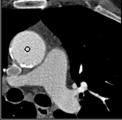

Samples for ascending aorta detection (black circle):

Cluster of candidate points in the ascending aorta.